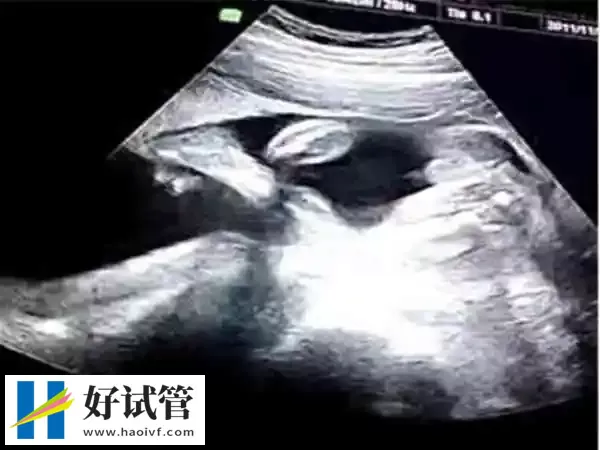

巴中试管婴儿移植35天孕囊偏小怎么办

在试管婴儿移植后35天孕囊偏小时,可以通过饮食调整、药物辅助和其他辅助措施来补救。比如适当的增加蛋白质和维生素摄入,有促进生长的作用;使用黄体酮、HCG和FSH等药物来促进孕囊的生长;同时避免过度剧烈运动,保持良好的心情,适当休息。然而每个人的情况不同,应根据具体情况咨询医生并遵循医生的建议。另外注意要定期的进行复查,如果孕囊在逐渐长大,则属于正常的状态。